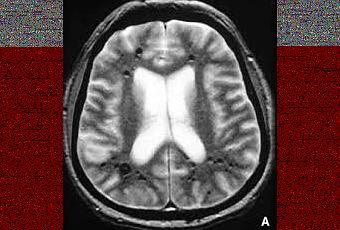

Imagerie en résonance magnétique (IRM) en T2 de lésions cavernomateuses.

Source iconographique et légendaire: http://association.gens.free.fr/NEUROLOGIA/EMC%20neurologie/